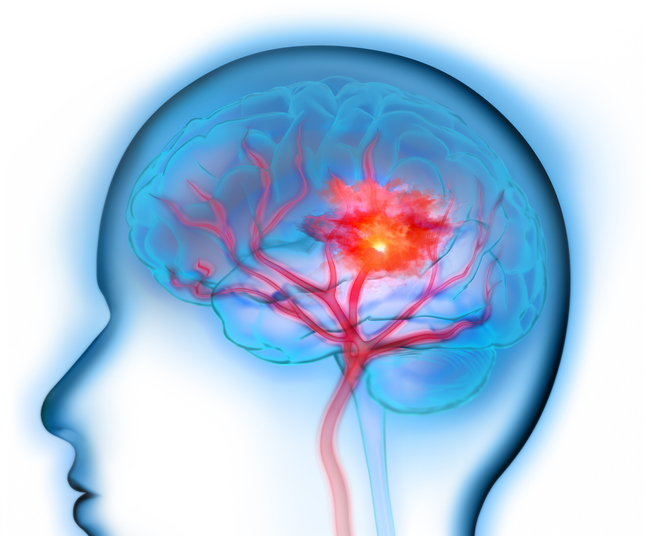

뇌출혈이란?

한국 사망원인 Top 5안에 들어갈 정도로 사망률이 높은 질환이라고 합니다. 뇌졸증은 뇌혈관이 터져서 손상이 나타나는 ‘출혈성 뇌졸증(뇌출혈)과 뇌혈관이 막혀서 나타나는 허혈성 뇌졸증(뇌경색)등으로 나뉠 수 있어요.

그 중에서 뇌출혈은 뇌 안에 있는 혈관인 뇌동맥에서 혈관 벽이 부풀어 올라 찢어지면서 혈액이 뇌 밖이나 안으로 흘러나와서 발생해요. 뇌동맥류가 파열되면 뇌와 척수 사이의 거미줄과 같이 생긴 공간에 혈액이 스며들게 되며 이런식으로 출혈이 일어나게 되면 30~절반이 사망에 이르게 돼요.